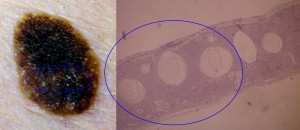

Melanin distribution is not always limited to basal keratinocytes. It is usually found in parallel with basaloid cell proliferation {Mishima, 1960}, melanophagic cells, are heavily present in the papillary dermis in deeply pigmented lesions.

This type often contains an amount of pigment superior in quantity than others. Indeed, one third of slides stained with hematoxylin-eosin {Becker, 1951} and two thirds of slides stained with silver {Lennox, 1949} contains an excess of melanin. As for the distribution of melanin, it is generally basally located, but all layers can be pigmented, and that in parallel with basaloid cell proliferation {Mishima, 1960}.

As for the dermis, inflammation characterized by a lymphomononuclear infiltrate is frequently present {Kao, 2000}. Melanophagic cells, are present in the papillary dermis proportionally with the quantity of pigment present{Kao, 2000}.

H. A skin disease sometimes considered as a variant of SK: Melanoacanthoma

{Pierson, 2003}Originally described by Bloch and then named type 1 non nevoid epithelioma {Mishima, 1960}, this type shows dendritic melanocytes packed with melanin {Simon, 1991}, which is absent in keratinocytes. This is probably due to a lack of transfer of melanin, although the mechanism is unknown {Tomich, 1990}.